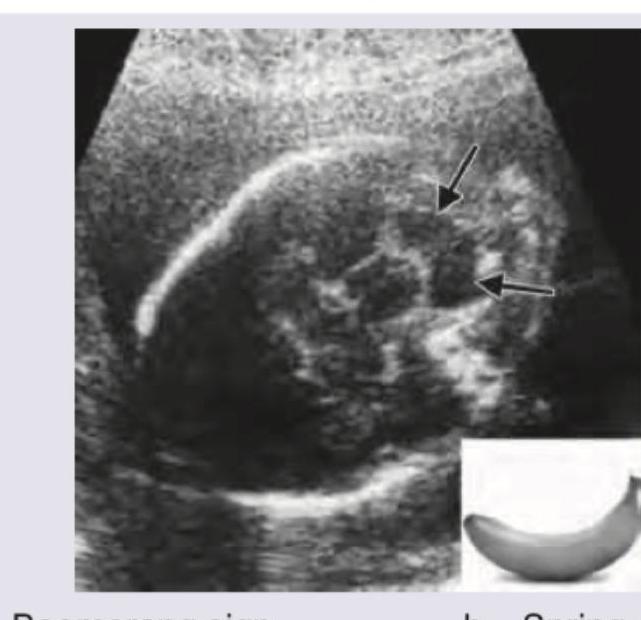

A pregnant woman undergoes a routine antenatal ultrasound scan in the second trimester. The sonologist notes an abnormal appearance of the fetal skull. What is the sign demonstrated in the given antenatal USG image?

Explanation: ***Lemon sign*** - The **lemon sign** refers to the shape of the fetal skull on ultrasound, where the frontal bones are indented, making the head appear lemon-shaped. - This sign is often associated with **Chiari II malformation** and spina bifida, where there is downward displacement of the cerebellar vermis and fourth ventricle. *Boomerang sign* - The **boomerang sign** is typically observed in imaging of the knee, referring to a meniscal tear where the displaced fragment resembles a boomerang. - It is not a sign used for fetal cranial abnormalities in ultrasound. *Spring coiled sign* - The **spring coiled sign** is a feature seen in intussusception on ultrasound, where layers of bowel are invaginated within another, resembling a coiled spring. - This sign is related to intestinal pathology, not fetal head anomalies. *Banana sign* - The **banana sign** describes the appearance of the cerebellum on fetal ultrasound when it is displaced or compressed due to Chiari II malformation, making it appear banana-shaped. - While also associated with Chiari II, the image provided shows the **head shape**, not the cerebellum, aligning with the lemon sign.